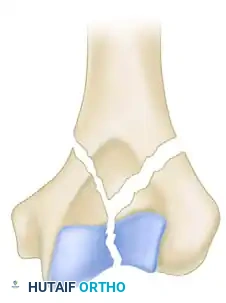

While the AO/OTA classification system is exhaustive (defining 61 types across A, B, and C categories), the Jupiter and Mehne classification, as well as the Mehne and Matta bicolumnar descriptions, offer superior utility for preoperative templating. Mehne and Matta categorize complex bicolumnar fractures based on their geometric configuration:

Mehne and Matta Y-Fracture configuration.